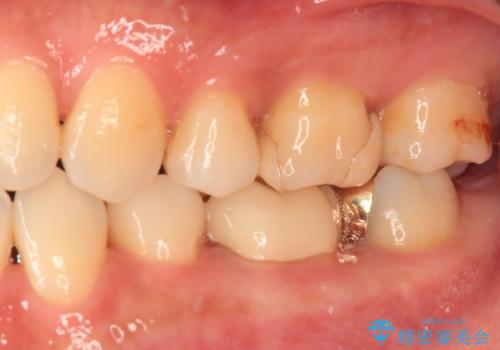

仮詰めのまま処置が進まないので転院 奥歯のむし歯治療

- 奥歯のむし歯処置を行っていたものの、しみて痛みが続く状態での経過観察が続いていたため、転院を希望して来院された患者様です。

痛みが続いているとのことで、むし歯が神経組織に及んでいる可能性があるため、処置を行うに当たりラバーダムによる唾液の排除を行うこととしました。

手前の歯はむし歯の範囲が広いためオールセラミッククラウンにて、最後方歯は部分的なむし歯であったのでPGAインレー(プラチナゴールドインレー)にて治療を進めることとしました。

仮詰めの状態が良くなかっただけで、むし歯が神経組織にまで及んでいることはなく、無事に治療を終えることができました。